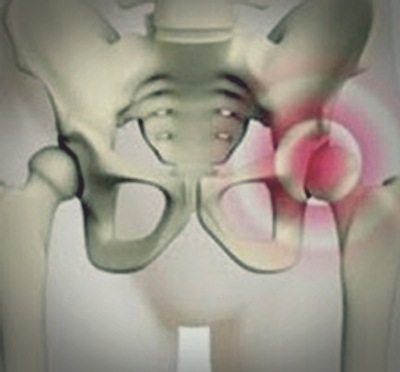

다리를 좌우로 벌리는 양반다리가 불편할 경우 고관절 충돌 증후군을 의심하는 것이 좋다. 혹시 나도 그런적은 없었는지 생각해보자. 고관절 통증의 원인은 크게 3가지 정도 된다.

첫째, 음주가 가장 큰 영향을 미치는 대퇴골두 무혈성괴사가 있다. 대퇴골두의 혈액 공급이 차단되면서 골두 부위의 뼈가 괴사 하는 질환이다. 두 번째는 선천성이나 퇴행성, 류미티스를 포함한 외상에 의한 감염 등으로 관절의 연골이 닳아 없어지는 고관절염이 있다. 마지막으로 고관절 충돌 증후군은 관절 가장자리 위치에서 뼈끼리 부딪히며 유발되는 통증으로 과도한 운동이나 움직임으로 우리 생활 속에서 쉽게 나타날 수 있다.